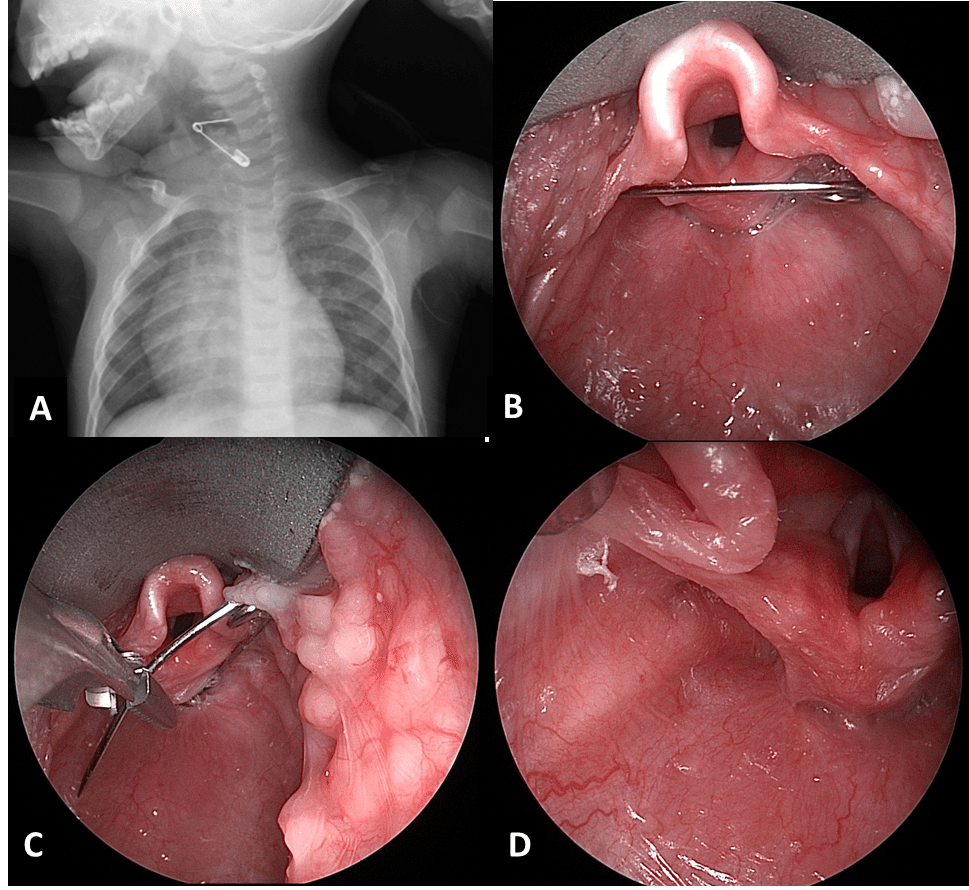

- إذا كان المعدن في المريء: يُجري الطبيب جراحة منظار لإزالته أو يعطى أدوية باسطة للعضلات حتى يُسهل نزول المعدن من المريء.

العملات المعدنية هي واحدة من العناصر الأكثر شيوعًا التي يبتلعها الأطفال ، إذا ابتلع طفلك عملة معدنية، اصطحبه إلى طبيب الأطفال أو إلى قسم الطوارئ في المستشفى قد تكون الأشعة السينية ضرورية للتأكد من أن العملة تمر عبر الجهاز الهضمي بشكل طبيعي.

- ممر الجهاز الهضمي هو ممر الأمان لأنه يعني تجاوز العملة المعدنية الجهاز التنفسي ووصولها للجهاز الهضمي وهنا يسهل التخلص منها عن طريق البراز بدون أي إجراءات أيا كان مكانها سواء في المعدة أو الأمعاء، وفي هذه الحالة لا يظهر على الطفل أي أعراض، حتى أن تنفسه يكون منتظم.

- و بخضوع الطفل لعمل أشعة “اكس” على البطن على أن يكون الطفل واقفا لتحديد مكانها فقط، خاصة أنها لن تتسبب في وجود أي مشكلة في الجهاز الهضمي، وأكد أنه لا يكاد يمر أسبوع إلا وقد تخلص الجسم منها.

- إذا علقت العُملة داخل موضع ما بالجسم ستظهر علامات على ذلك من العلامات القئ، وألم الصدر والبطن إذا كانت عالقة في المرئ أو المعدة. أما إذا علقت على جدار الأمعاء فقد تؤذي الجدار، ومن علامات وجودها في ذلك الجزء وجود صوت غريب عند إخراج البراز أو وجود نزيف معه. من الهام أن يلجأ الآباء إلى الطوارئ، وألا تتم محاولة إخراج العُملة بالإصبع لأن ذلك سيضر الطفل أكثر.

- عند حدوث هذه الحادثة، أو الشك في حدوثها، لا ينبغي الانتظار وإنما طلب الطوارئ على الفور، وإجراء الفحص بالأشعة السينية (إكس)، واتباع التعليمات الطبية.